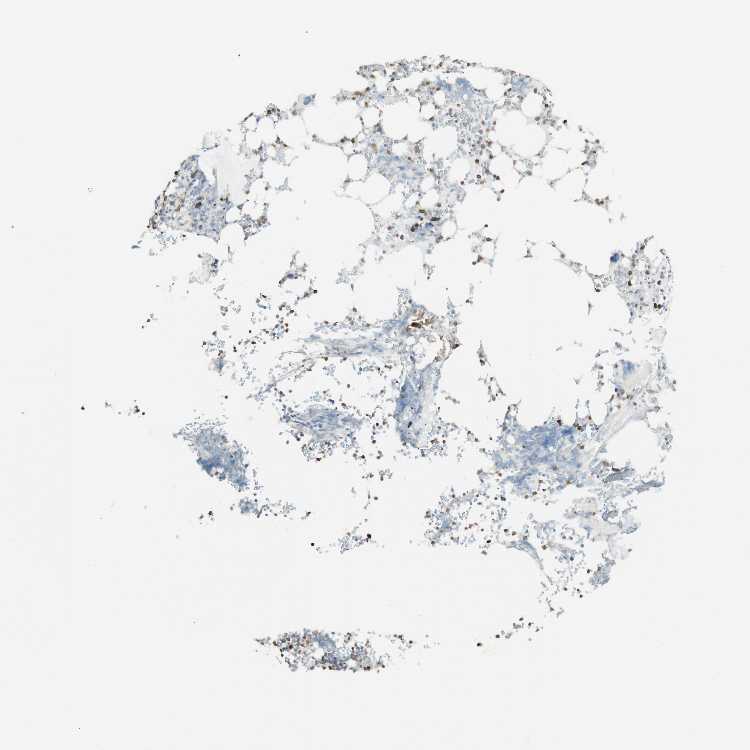

BONE MARROW - Antibody stainingi

Antibody staining in the annotated cell types in the current human tissue is reported as not detected, low, medium, or high, based on conventional immunohistochemistry profiling in selected tissues. This score is based on the combination of the staining intensity and fraction of stained cells.

Each image is clickable and will lead to virtual microscopy that enables deeper exploration of all samples and also displays staining intensity scores, fraction scores and subcellular localization as well as patient and tissue information for each sample.

Antibody HPA004919Antibody HPA005679

Hematopoietic cells MediumNot detected